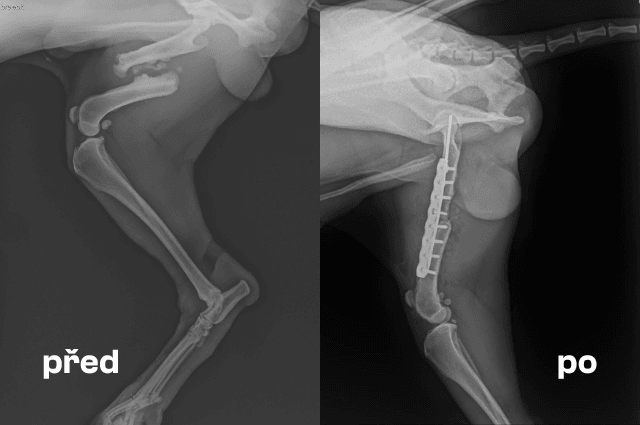

Veterinární vyšetření potvrdilo těžkou zlomeninu stehenní kosti. Byla nutná okamžitá operace, která naštěstí proběhla hladce. Pes je nyní stále v péči kliniky, čeká ho vyjmutí stehů a následný rentgen, aby se ověřilo, že se kost hojí správně.